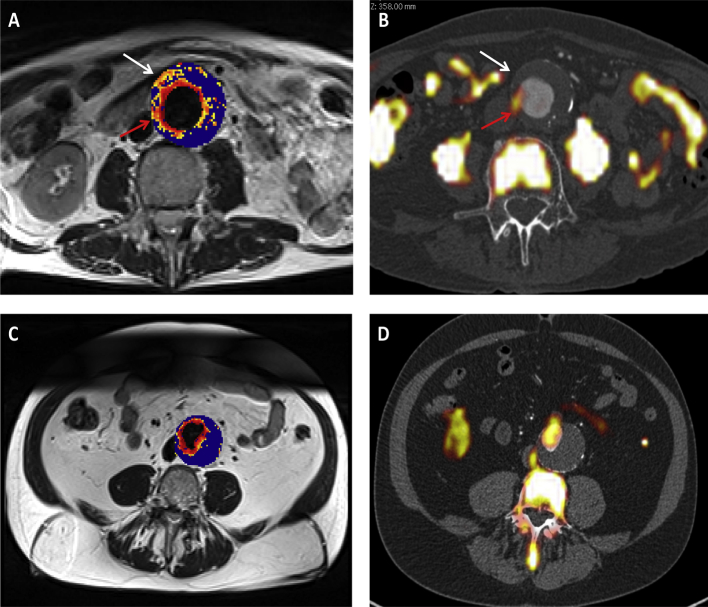

Classification of AAA according to 18F-FDG or USPIO uptake using the quadrant technique was consistent and reproducible with excellent inter-observer agreement and a kappa statistic of 0.87 for 18F-FDG and 0.85 for USPIO. On occasion, areas of increased USPIO and 18F-FDG uptake co-localised to the same quadrant in the aortic wall, although regions of USPIO uptake without corresponding 18F-FDG uptake were also commonly seen (Fig. 2). Overall, co-localisation of areas of increased USPIO and 18F-FDG uptake were poor (kappa statistic 0.074; 95% CI 0.026–0.122) and there were more areas of increased uptake identified on MRI than on PET-CT (Table 3). Focal and discrete uptake of USPIO can be readily discerned on MRI, whereas there was more diffuse and ill-defined uptake of 18F-FDG involving both the wall and the thrombus on PET-CT.

Figure 2.

(A,B) Representative magnetic resonance imaging (MRI) (A) and fused positron emission tomography and computed tomography (PET-CT) (B) scans from the same patient with an abdominal aortic aneurysm (AAA). Ultrasmall superparamagnetic particles of iron oxide (USPIO) uptake, defined by percentage change in T2* is demonstrated using a colour scale. Changes in T2* value over the threshold (59%) are presented on a graduated (yellow-red) colour scale and data below the threshold appears blue. Corresponding 18F-fludeoxyglucose (FDG) activity (red arrow) can be seen in B. Differences in the location of regions of uptake between the techniques are apparent, as marked by the white arrow. (C,D) are corresponding MRI and fused PET-CT slices from the same patient who has no USPIO or 18F-FDG uptake in the wall of the AAA, with uptake limited to the peri-luminal area.